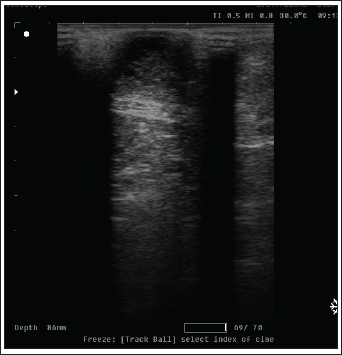

Ultrasonography

On ultrasound images, mammary gland tissue showed higher echogenicity than normal tissue. The FMH lesions were well-defined, slightly hyperechoic, lobulated masses containing multiple small anechoic clefts within the mammary parenchyma.

The intraductal pattern is dominant, with anechoic areas corresponding to clefts of different shapes within the mammary gland parenchyma. The presence of clefts in mammary fibroepithelial lesions provided a more heterogeneous appearance to the ultrasound images (Fig. 4). In the solid lesions, the ultrasound pattern is more homogeneous (Fig. 5).

Fig. 5. Ultrasonographic image of a solid pattern lesion.

Radiology was of little interest in cases of FMH, as lateral abdominal surveys only reveal the enlargement of the mammary glands with an intact body wall (Burstyn, 2010). In comparison, ultrasonography provides more valuable information about the assessment of lesion pattern and echogenicity. Similar findings have been reported (Payan, 2013). In the present study, medical treatment was administered to 25 cats using cabergoline drug administration (5 µg/kg once daily PO), which proved effective in the majority of treated cats, leading to substantial regression of mammary size within three to 6 weeks, as previously reported (Giménez et al., 2010; Akkuş and Yaprakcı, 2024).